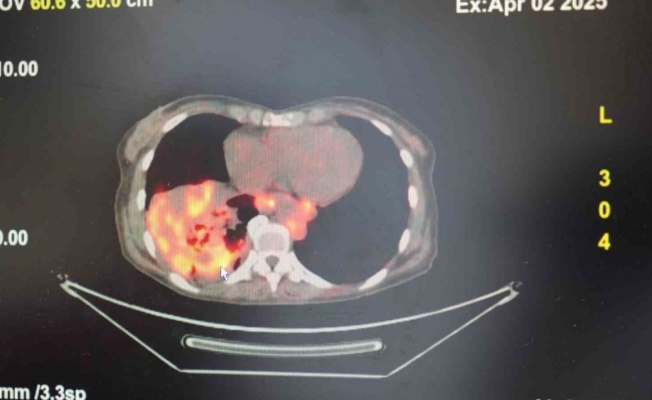

Samsun’da, nadir görülen kalıtsal moyamoya hastalığı ve her iki şah damarı tıkalı olan bir hastaya, çalışan kalpte pompa destekli üç damar koroner bypass ameliyatı başarıyla gerçekleştirildi. Literatüre göre bu özellikteki vaka, dünyada bildirilen 3. vaka, Türkiye’de ise yapılan ilk operasyon olma özelliğini taşıyor.